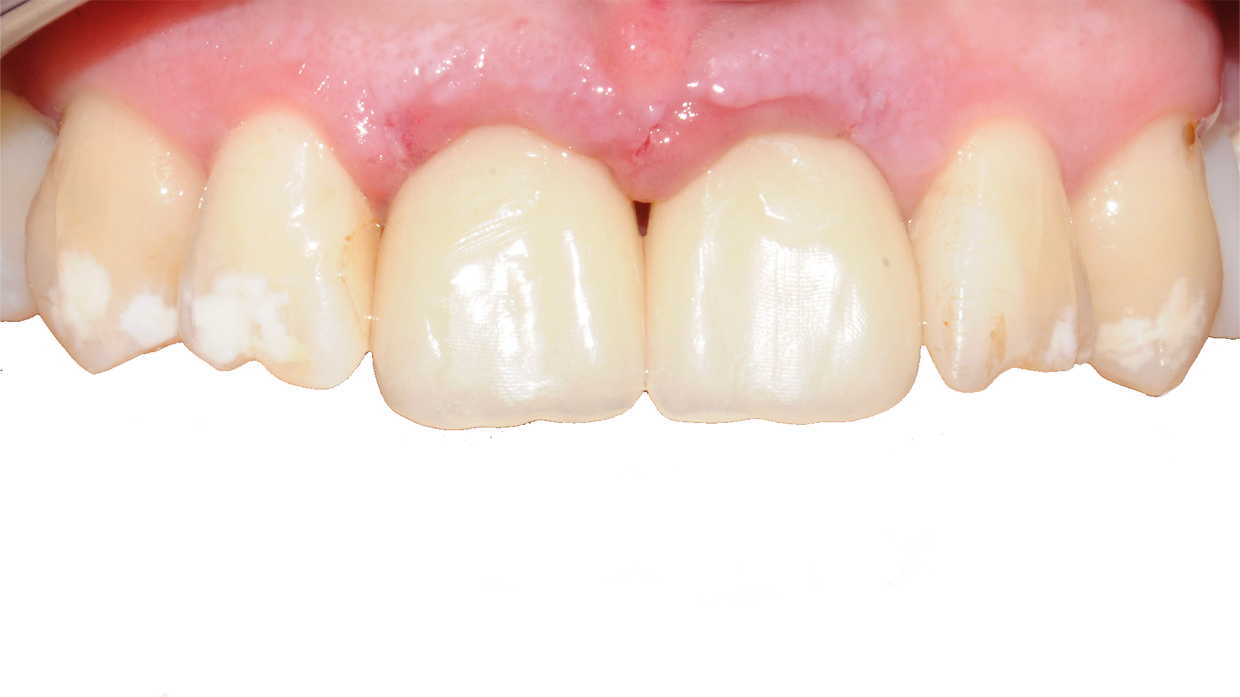

Il posizionamento degli impianti è stato pianificato prima dell'intervento su un software dedicato. In un'unica seduta, dopo l'estrazione degli elementi dentari compromessi, sono stati immediatamente inseriti gli impianti nella posizione pianificata, grazie alla realizzazione della dima chirurgica. Per ridurre il riassorbimento osseo a lungo termine e garantire quindi una maggiore resa estetica (vista la zona d'intervento), la chirurgia è stata eseguita con una particolare tecnica denominata: Socket Shield Technique.